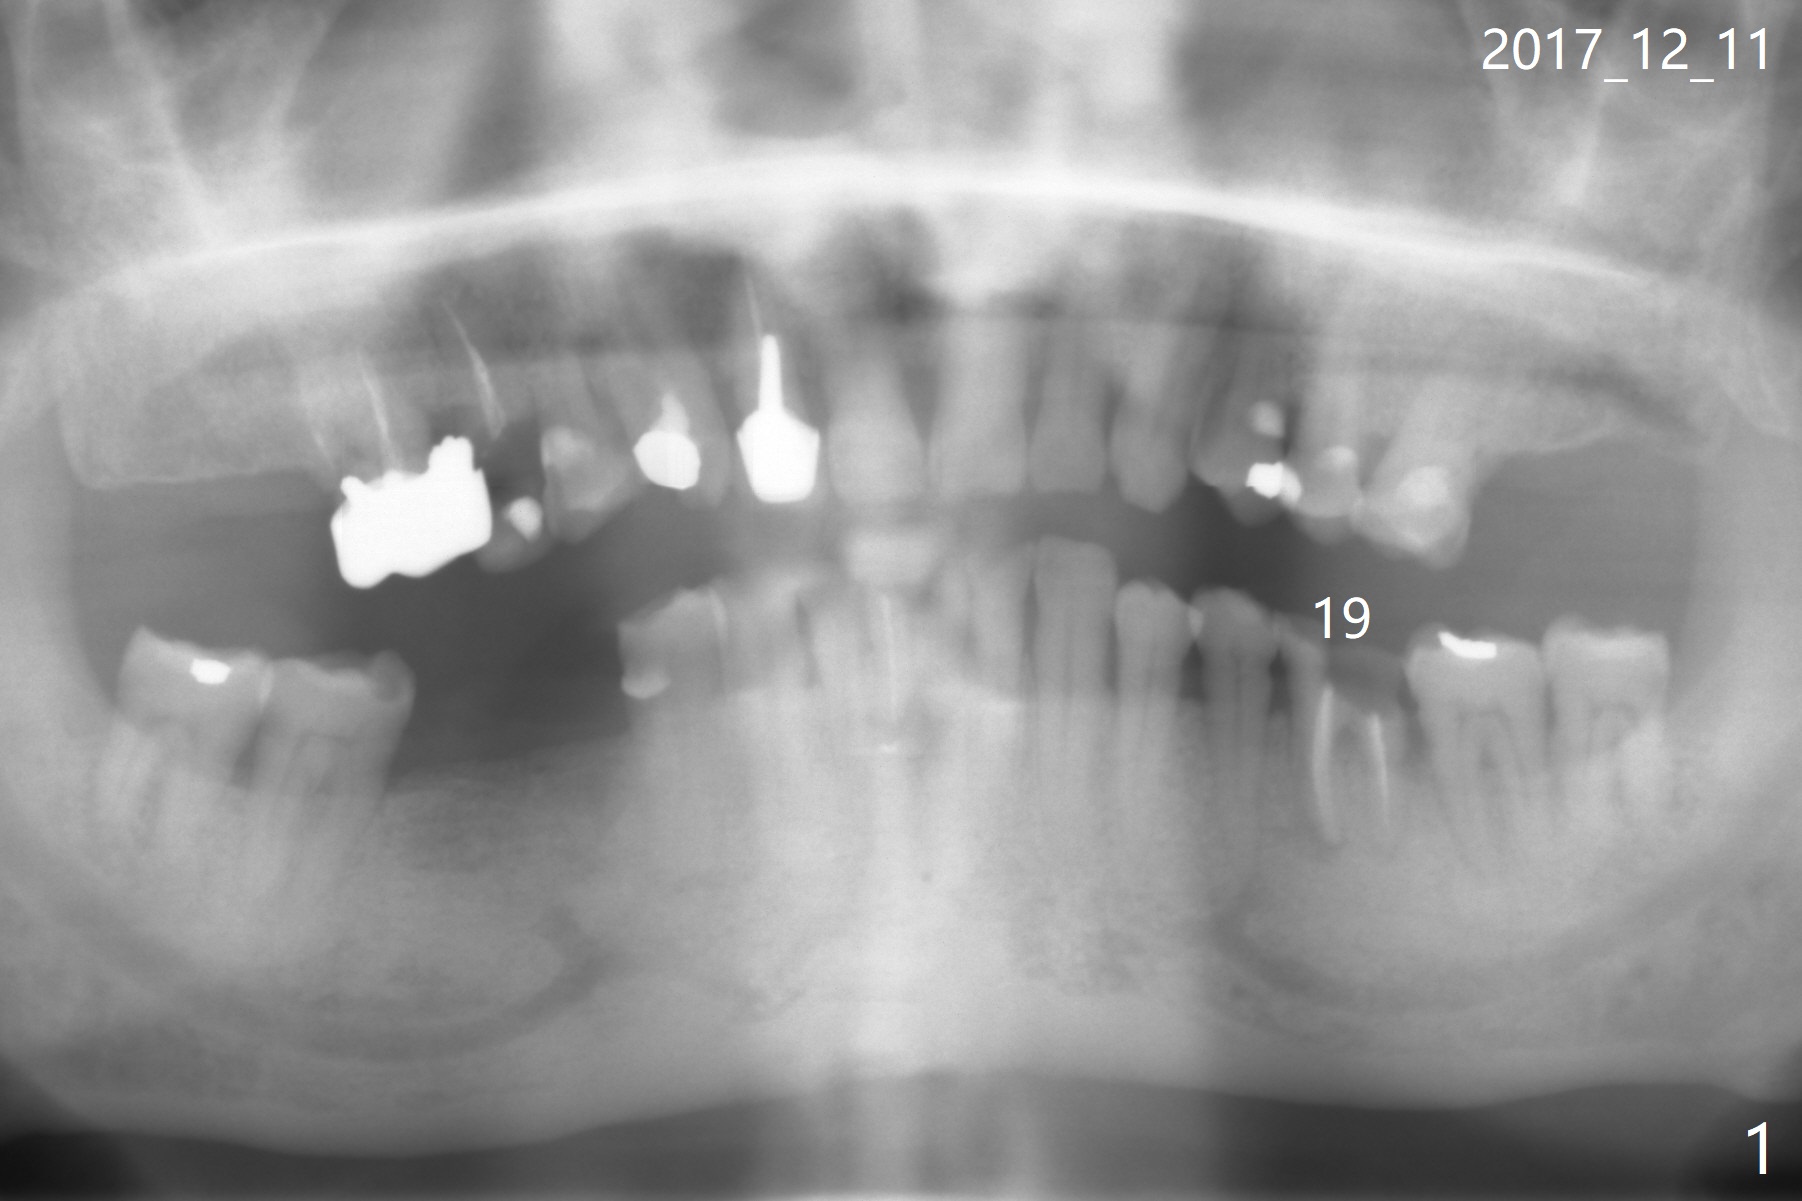

A 73-year-old man (with history of lung cancer with chemotherapy 6 years ago) requests removing the tooth #19 (Fig.1) with the loose mesiolingual fragment (Fig.2 ML). The mesiobuccal plate is low when the tooth is extracted. The septum should provide additional blood supply to bone graft to facilitate healing (Fig.3 S, as compared to the case without it). After placement of 6-month membrane and suturing, acrylic dressing is applied, which is stable 9 days postop (Fig.4 A). The acrylic dressing remains in place 1 month postop (Fig.5). After wiggling, it dislodges fairly easily. The socket heals with slight atrophy (Fig.6).